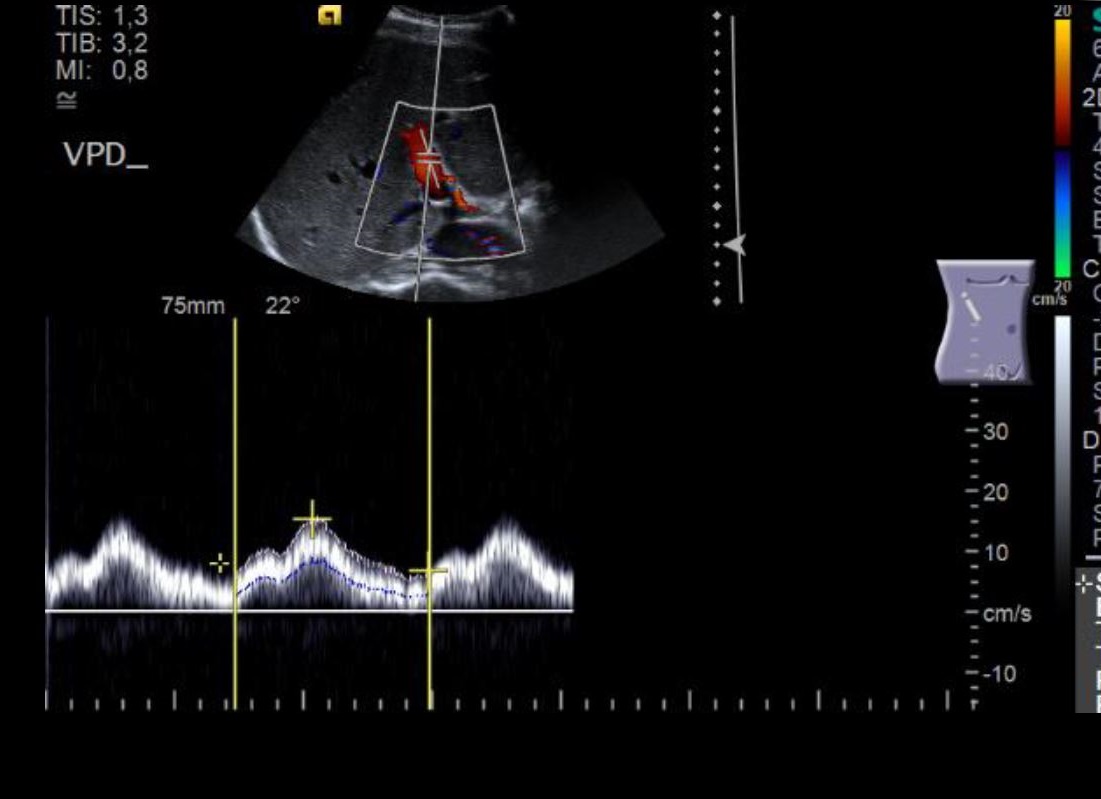

Zusätzlich erfolgt eine Beurteilung von Gefäßen: Hauptschlagader („Aorta“) und Hauptvene sowie die großen abgehenden Äste der Aorta (versorgende Arterien für Leber und Milz, die Nieren und den Darm). Auch die Durchblutung der Leber sowie der Nieren wird dargestellt und vermessen. Ferner können vergrößerte Lymphknoten erkannt werden.

Zum Anderen kann die Flussgeschwindigkeit des Blutes gemessen werden – damit errechnet man z.B. das Ausmaß einer Gefäßverengung.

Aber der Ultraschall kann nicht nur verschiedene Gewebearten differenzieren, er kann auch ruhende von bewegten Strukturen unterscheiden. Hier kommt die „Doppler-Methode“ (nach dem österreichischen Physiker Christian Andreas Doppler) ins Spiel, mit der man z.B. fließendes Blut entdecken und sogar die Flussgeschwindigkeit messen kann: Das Signal verändert sich, je nachdem, ob und wie schnell der Blutstrom sich auf den Schallkopf zu oder von ihm wegbewegt. Dies wird durch eine Geräusch kodiert (Doppler-Sonographie) oder mit unterschiedlichen Farben belegt (Farbdoppler) – das ergibt dann die bekannten bunten Bilder.